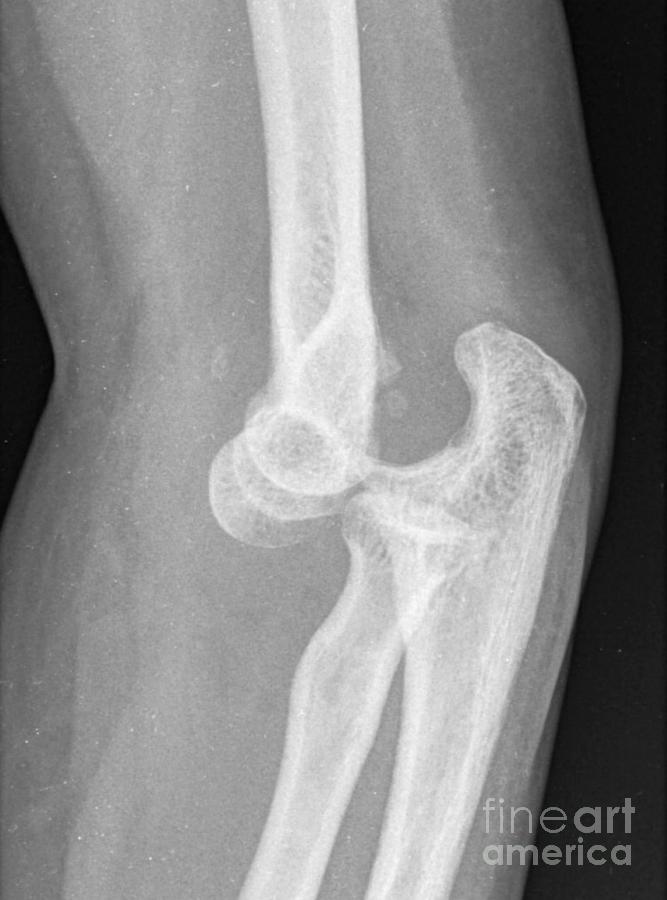

From fineartamerica.com

Dislocated Elbow, Xray Photograph by Du Cane Medical Imaging Ltd How Serious Is A Dislocated Elbow Elbow dislocation complications may involve bone fractures,. At home, put ice on the elbow. Dislocated elbows are considered medical emergencies. Nerves that run through or near the elbow, such as the ulnar, median, and radial nerves, can be affected during an elbow. An elbow dislocation should be considered an emergency injury. A dislocated elbow occurs when the elbow bones no. How Serious Is A Dislocated Elbow.